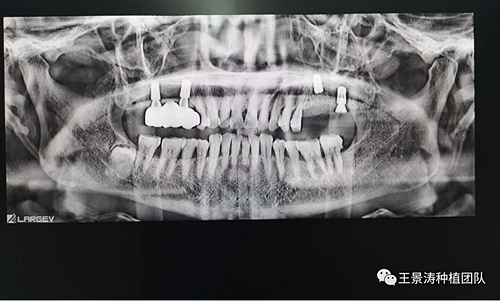

左側(cè)下頜第二磨牙及右側(cè)下頜第一磨牙同時(shí)即刻種植病例?;颊吣贻p女性,無系統(tǒng)性疾病。37及46殘冠及殘根,且46劈裂,無法冠修復(fù),必須拔除。37根尖慢性炎癥,大量肉芽組織存在,46根分叉較高,根分叉骨質(zhì)尚可。CBCT示:根尖骨質(zhì)至下牙槽神經(jīng)管距離可滿足種植體的初期穩(wěn)定性,遂考慮即刻種植,并在種植體周邊填入骨粉并覆蓋骨膜,雙側(cè)的種植體初期穩(wěn)定性相差無幾,但考慮到37根尖慢性炎癥較大,遂給予埋入式種植。